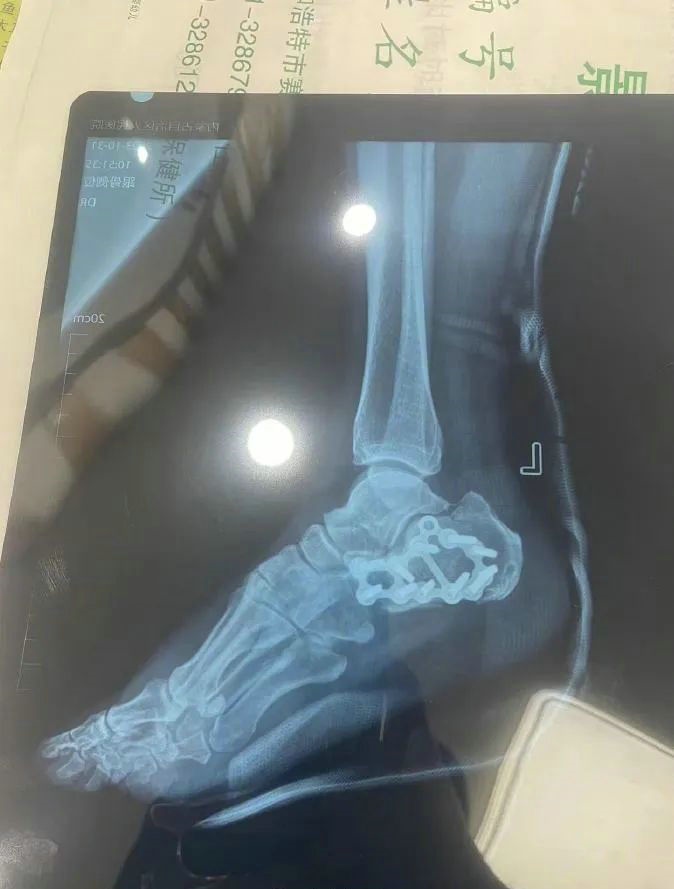

“那時候我剛工作了兩天,在第三天10月22日下午施工過程中從三層高的鐵架上摔了下來,導(dǎo)致30厘米左右的鋼筋刺穿我的右側(cè)臀部,左腳跟也粉碎性骨折,被送往內(nèi)蒙古自治區(qū)人民醫(yī)院救治,當(dāng)晚做了手術(shù)取出刺在右臀部的鋼筋,10月30日又進行了左腳粉碎性骨折手術(shù)?!崩紫壬嬖V記者。